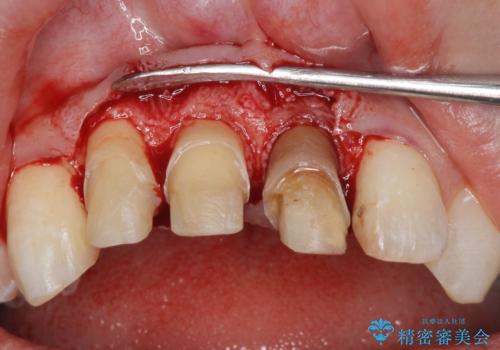

・歯肉縁下カリエス →部分矯正による歯の挺出・歯周外科

歯の挺出を行ったことで歯ぐきの腫れも改善され、安定した歯周環境下でのセラミッククラウン治療を行うことができました。